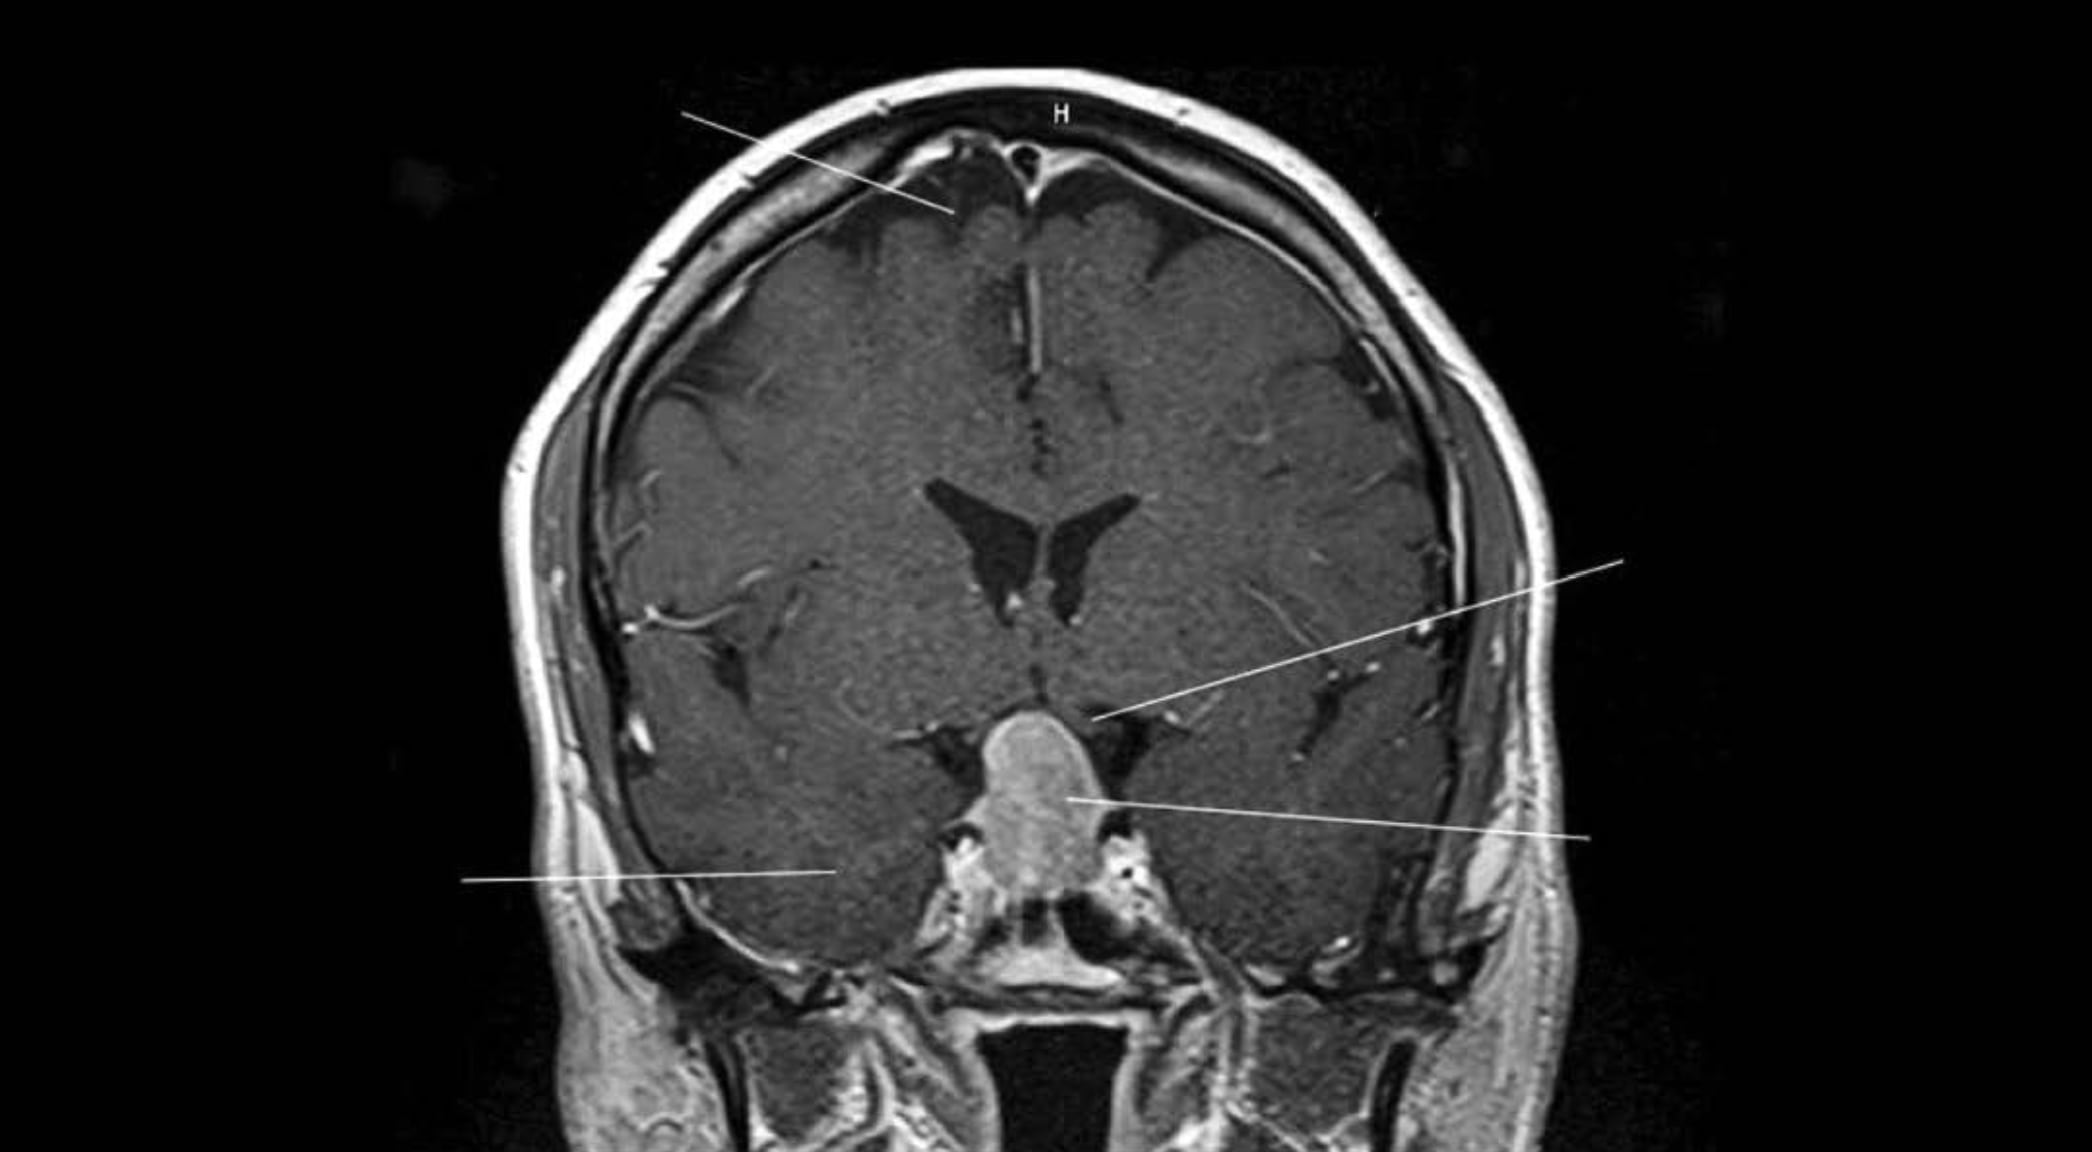

2015년에 찍었던 첫 *PET 스캔이 특히 흥미로웠는데,

뇌 전체에 아밀로이드가 쌓여 있었고

그 중에서도 후각 영역 여러 곳에서 두드러지게 나타났습니다.

그걸 보면서 ‘정말 멋지다’라고 말했던 기억이 납니다.

병리학적 소견과 신경해부학이 맞아떨어지는 광경에 우리 모두가 무척 흥분했었죠.”

사실 *MRI에서 뭔가 나타날 거라는 예상은 못 했어요.

처음에 저의 뇌 스캔 파일을 혼자 열어보고 충격을 받았습니다.

탁구공 크기만 한 종양 덩어리가 보였으니까요.

내 뇌에 암이 생기다니,

완전히 망했군… 솔직히 곧 죽을 거라고 생각했습니다.

다행히 양성이었고 성가신 수술 정도로 제거할 수 있었어요.

뇌하수체 종양을 제거한 뒤로도 후각은 나빠졌고 몇 년 뒤에는 후각이 완전히 사라졌어요.”

MRI : 자기공명영상_Magnetic Resonance Imaging의 약자로,

강한 자기장과 전파를 이용해 인체 내부를 자세히 촬영하여 검사를 하는 시스템을 말함.